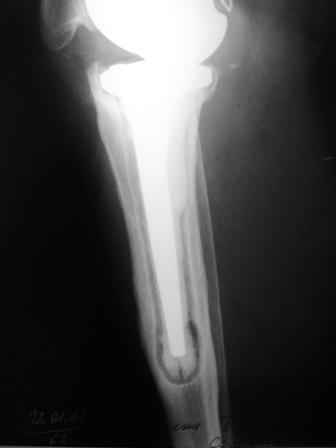

Уважаемые коллеги!Хотелось бы услышать Ваше мнение о возможности и способе помощи больной. 1939 г.р. В 1995г. эндопротезирование правого коленного сустава протезом Феникс, в 1999г. в г. Томске - ревизия - ротационный хинч W.Link. C 2005г. прогрессирует варусная деформация за счетнестабильности тибиального компонента. Попытка ортезирования - без эффекта. Попытка направить в ФСМУ без эффекта, да и больная не хочет никуда ехать.С уважением, Leonid

Технически можно надеть гвоздь на ножку протеза

Понятно что для решения на операцию артродеза необходимы веские причины. Но я не уверен что здесь асептическое расшатывание. Судя по снимкам, бедренный компонент стоит не плохо, и есть рассасывание костной ткани вокруг всего протеза в голени. Что-то мне подсказывает об инфекционном процессе, возможно вялотекущем. В наших условиях я сделал бы обследование включающее анализы крови с СОЭ, СРБ. Сделал бы пункцию коленного сустава или даже биопсию мягких тканей для посева и микроскопии.